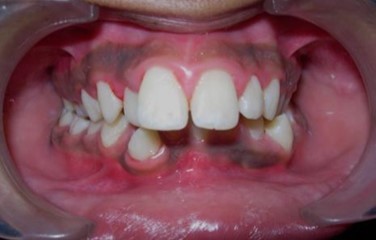

Intraoral assessment. (Figure 1d,Figure 1e,Figure 1f,Figure 1g,Figure 1h).

Figure 1d.Pre-treatment intra-oral-Frontal

The maxillary arch was V-shaped with severely proclined and rotated maxillary incisors with a palatally placed 12. The mandibular arch was U-shaped with severe crowding of mandibular incisors, with 43 partially erupted and buccally placed with transpositioned 42 and 43, with 42 mesiolingually rotated, 33 distolingually rotated and 34 distolingually rotated and buccally placed.

Severe increase in overjet and deep bite were both observed. The maxillary midline coincided with the skeletal midline but the mandibular midline was shifted to the right side by 1 mm. Bilateral maxillary posterior crossbite was also observed. On right side the molar relation was Class I and on the left side it was Class II. The canine relation was Class II on the left side and the curve of Spee was increased.